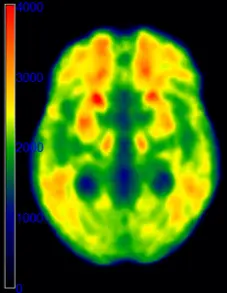

We use a broad range of magnetic resonance imaging techniques (MRI) and positron emission tomography (PET). To reach a better understanding of the neural underpinnings of cognitive performance, we use advanced techniques and methods such as:

High iron load in the brain, deleterious to brain integrity and cognitive performance, has been observed in normal and pathological aging. We investigate the impact of brain iron on neural activity and cognitive performance in aging. Another aim is to uncover the genetic, physiological and lifestyle determinants of brain iron accumulation.

We assess the role of brain iron and microbleeds in cognitive and physical function in a population-based study on aging (SNAC-K). One aspect of this project is the automated segmentation of iron-rich small nuclei using deep learning.